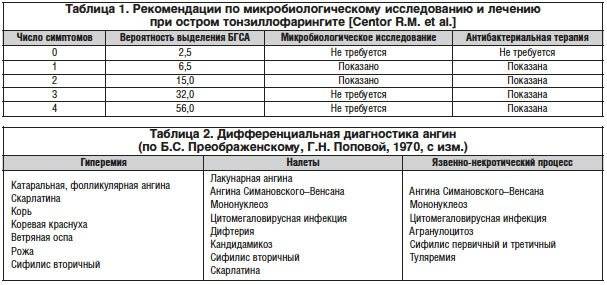

При проведении микробиологического исследования посева с поверхности миндалин выявляют следующих возбудителей тонзиллита:

- 30-40% бета-гемолитический стрептококк группы А;

- 28-30% стрептококки группы С и G;

- 20-25% стафилококки;

- 5-22% иные микроорганизмы: нейссерия, микоплазма, пневмококк и др.

Наиболее часто бактериальная или гнойная ангина у детей вызывается бета-гемолитическим стрептококком группы А. Причина заключается, прежде всего, в его строении: они несут капсулы (М-белок) для адгезии к слизистой оболочке миндалин. Эти микроорганизмы устойчивы к фагоцитозу и выделяют различные экзотоксины. Последние приводят к выработке антител, которые перекрестно действуют еще и на сердечную мышцу, ткань сосудов, суставов и почечную паренхиму.

Бета-гемолитический стрептококк часто встречается в детских садах и школах. Наибольшей активностью обладает в осенне-зимний период, что приводит к росту заболеваемости именно в это время года.